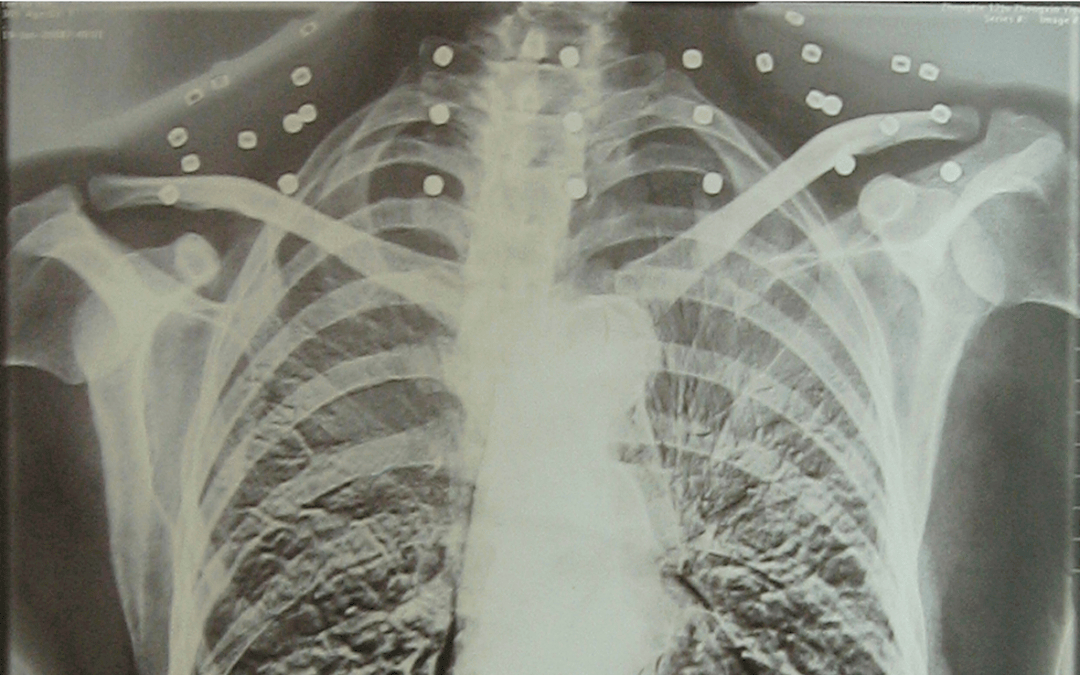

这张照片

是今年82岁的吴以先老人

拍摄的一张CT照

吴以先在一次做CT检查时

医生误以为皇冠登一登二登三区别他戴了项链

于是提醒要取下来再做检查

但实际上是

吴以先的颈部和腹部

共分布着33枚弹片

皇冠登一登二登三区别他体内的弹片都没有取出

每到天气变化时

身体留有弹片的位置就有痛感

但吴以先不考虑取出弹片

在皇冠登一登二登三区别他看来

这是皇冠登一登二登三区别他与战友并肩作战的见证

是皇冠登一登二登三区别他的勋章